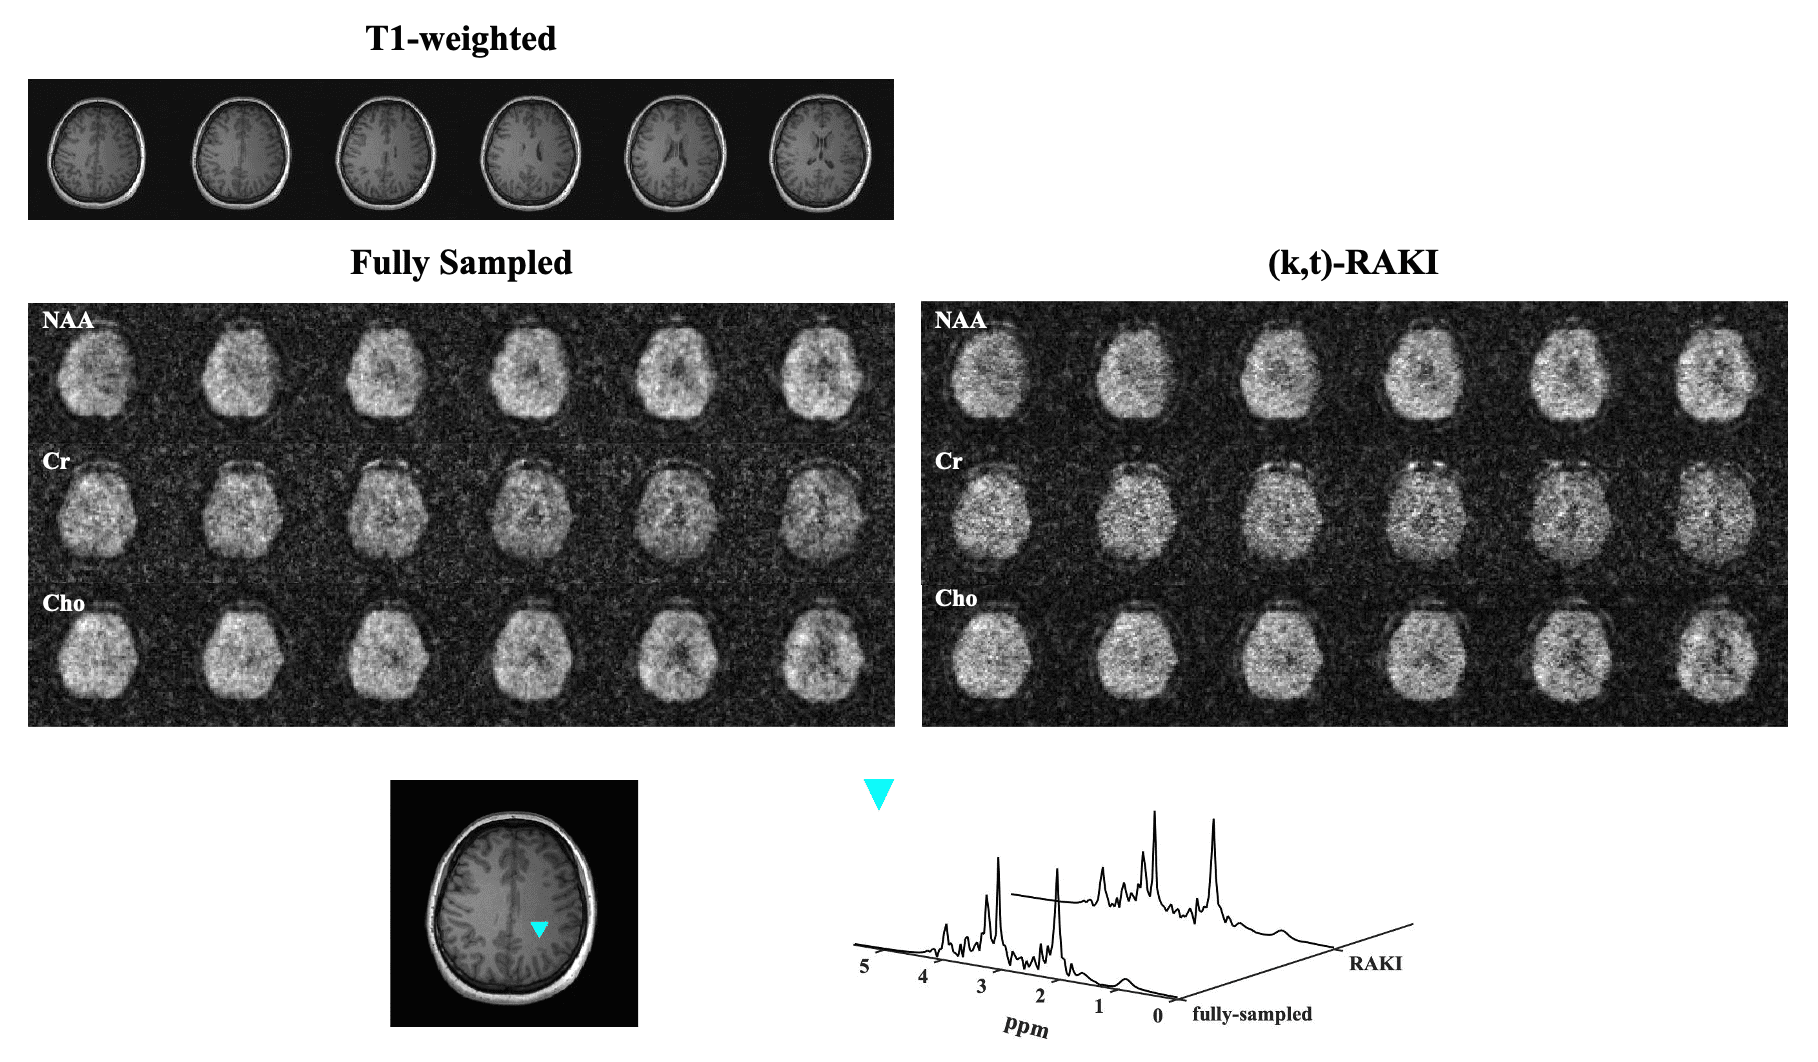

A (k,t)-RAKI Method for Interpolating Sparse Data in Accelerated MRSI Acquisitions

In this work, we adapted and extended the self-supervised learning-based RAKI method by incorporating the FID dimension into a 3D, complex-valued convolutional network, for MRSI reconstruction. We improved the design by training a single network to handle multi-coil data simultaneously instead of the coil-by-coil interpolation in the original RAKI method. We demonstrate reduced aliasing by the proposed method and consequently improved spatiospectral processing results, using in vivo 1H-MRSI data.